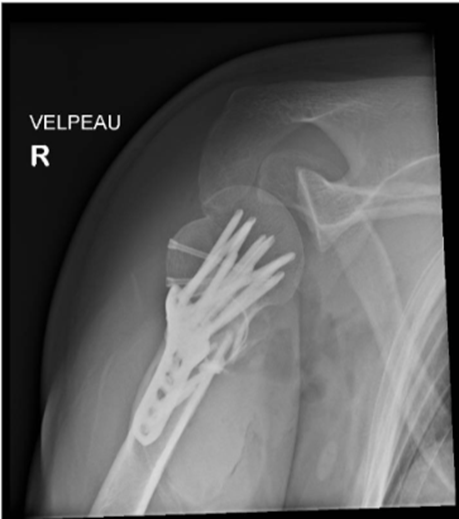

We present a 50-year-old Southeast Asian male who presented to the emergency department with right shoulder pain and deformity. This closed injury was sustained after colliding with a rock while cycling, in which the patient fell off his bike and landed onto his right shoulder. Neurovascular status was intact, and radiographs of the right shoulder revealed a 4-part right proximal humerus posterior fracture-dislocation with head split (AO Classification 11-C3) (Image 1). During the consultation, the options of surgical fixation and hemiarthroplasty (HA) were both explained to the patient. The risk of AVN leading to salvage arthroplasty was discussed for fixation, whereas the concerns of implant longevity and dislocation risk was discussed for arthroplasty. In view of the displaced fracture, shared decision making between surgeon and patient was made for surgery to facilitate early mobilisation. Considering the patient’s age and activity level, fixation will be attempted. However, the patient was counselled on the possibility of shoulder hemiarthroplasty should the intraoperative findings reveal a fragmented fracture pattern to prevent AVN, or an unfavourable fracture pattern in which fixation is unlikely to be successful. One key limitation of Hertel’s study to predict the risk of AVN is the presence of few young patients (mean age of the study participants were 60 years old) [18]. This also influenced the surgeon’s decision to offer joint preserving surgery to the patient. A computed tomography scan was not necessary since the severity of the fracture-dislocation is evident on radiographs.

A. Anteroposterior (AP) view

B. Valpeau view

C. Lateral/ Y scapula view

Image 1: Preoperative imaging of the right shoulder showing a right proximal humerus posterior fracture-dislocation with head split.